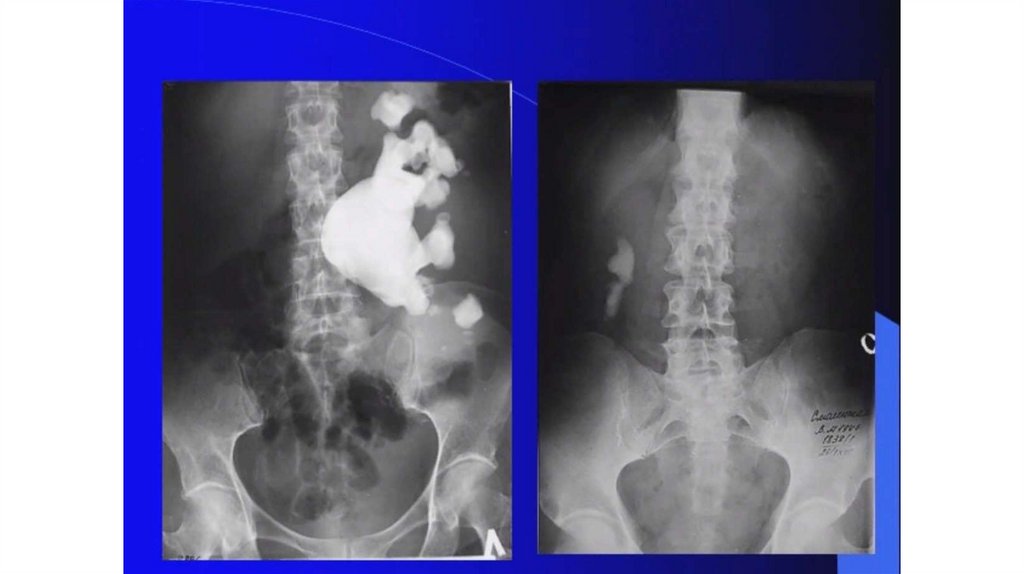

Мочекаменная болезнь. Мочекаменная болезнь и беременность

Мочекаменная болезнь